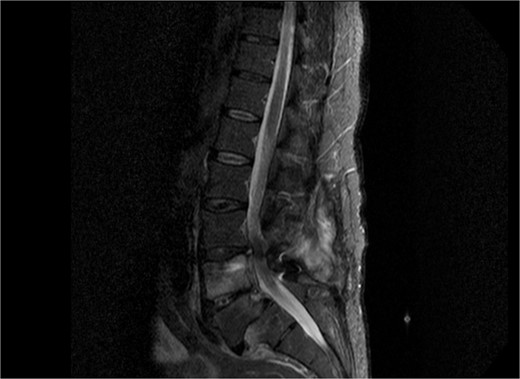

As shown in Table 1, the patient’s blood tests were compatible with infection and an MRI-CT scan was ordered to confirm or exclude the participation of lumbar spine. Subsequently, the MRI revealed signs compatible with the diagnosis of osteomyelitis involving the L4 and L5 vertebra as shown in sagittal view in Fig. 1 where screws were placed, with the presence of pathological collection of fluid around the pedicle screws and diffuse soft tissue edema as shown in the axial view in Fig. 2. Additionally, the CT scan revealed septic loosening of the pedicle screws. Immediately the patient underwent surgical irrigation and debridement with placement of new larger pedicle screws due to the absence of union. Intraoperatively eight different samples were collected for culture from the surrounding soft tissue and bone, while the previous pedicle screws were sent for sonication. Postoperatively all the blood cultures were negative along with the soft tissue and bone, only the sonication revealed infection with P. asaccharolyticus

Sagittal view of MRI of lumbar spine demonstrating diffuse soft tissue pathological sign, with signs of osteomyelitis at the level of L4 and L5.